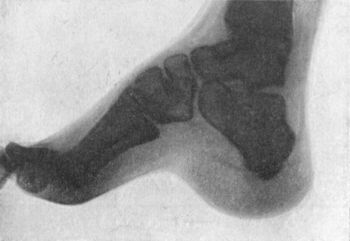

151.Radiogram of Foot of Adult, showing Changes in the Bones in Pes Cavus286